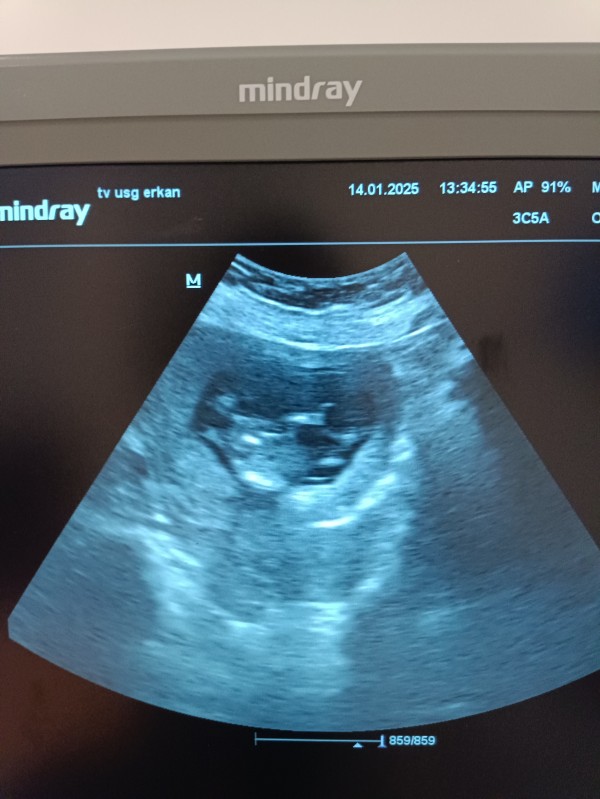

12+4haftalık cinsiyet tahmin lütfen :))

İcimden kiz gibi geldi

Boş sanki bacak arası

Görüntü  net değil bilemedim